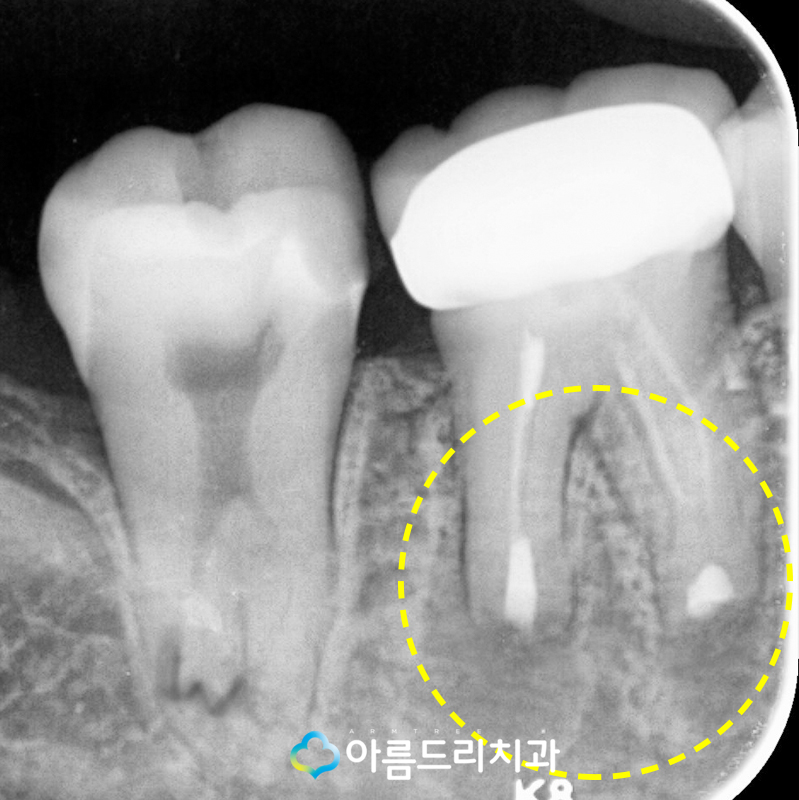

보다 정확한 위치의 확인을 위하여 CT를 찍어 보았는데요. 역시나 예상한 것과 같이 X-ray 상에서 검게 보였던 치아뿌리쪽에 문제가 발생 하여 잇몸고름주머니가 생성된 것을 확인할 수 있었으며 보통 잇몸에 고름이 나오는 경우라면 치근단절제술을 통해 염증을 깨끗하게 제거해 야 하겠지만 어금니쪽은 치근단절제술을 할수 없기 때문에 치아재식술 치료를 시행하기로 결정하게 되었고 치아재식술의 경우 치아를 발치하는 과정에서 치아가 부러지거나 크랙이 발생할 수도 있기 때문에 환자분께 치아재식 술에 대한 충분한 설명을 드리고 진행합니다.

1주일 뒤 환자분의 사진을 보니 검은색이었던 치아의 뿌리쪽이 점점 밝은 색으로 변하며 사 진상으로도 확연히 보이는 정도로 점차적으로 잇몸의 염증이 없어지고 다시 원래의 상태로 치유되고 있는 모습을 확인하실 수 있습니다.